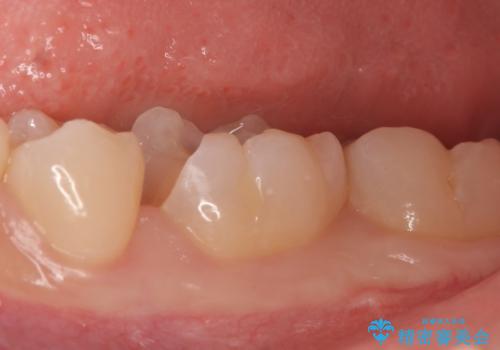

古い樹脂と虫歯を除去後、セラミックインレーによる修復を行いました。

当院のセラミックインレーはemaxという強度と審美性に優れた材料を使用しています。

またプレス方式でインレーを製作しているため、削り出しで製作するCADCAMより優れた適合性も持ち合わせており、虫歯が再発しにくい修復物です。